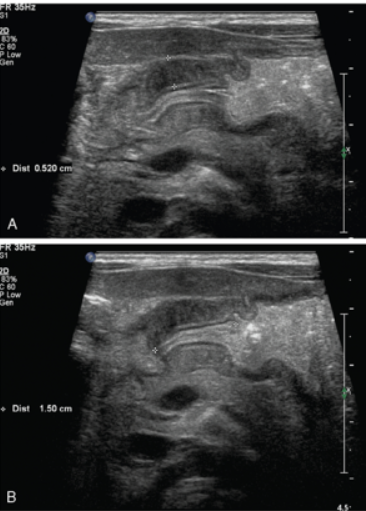

Acute appendicitis